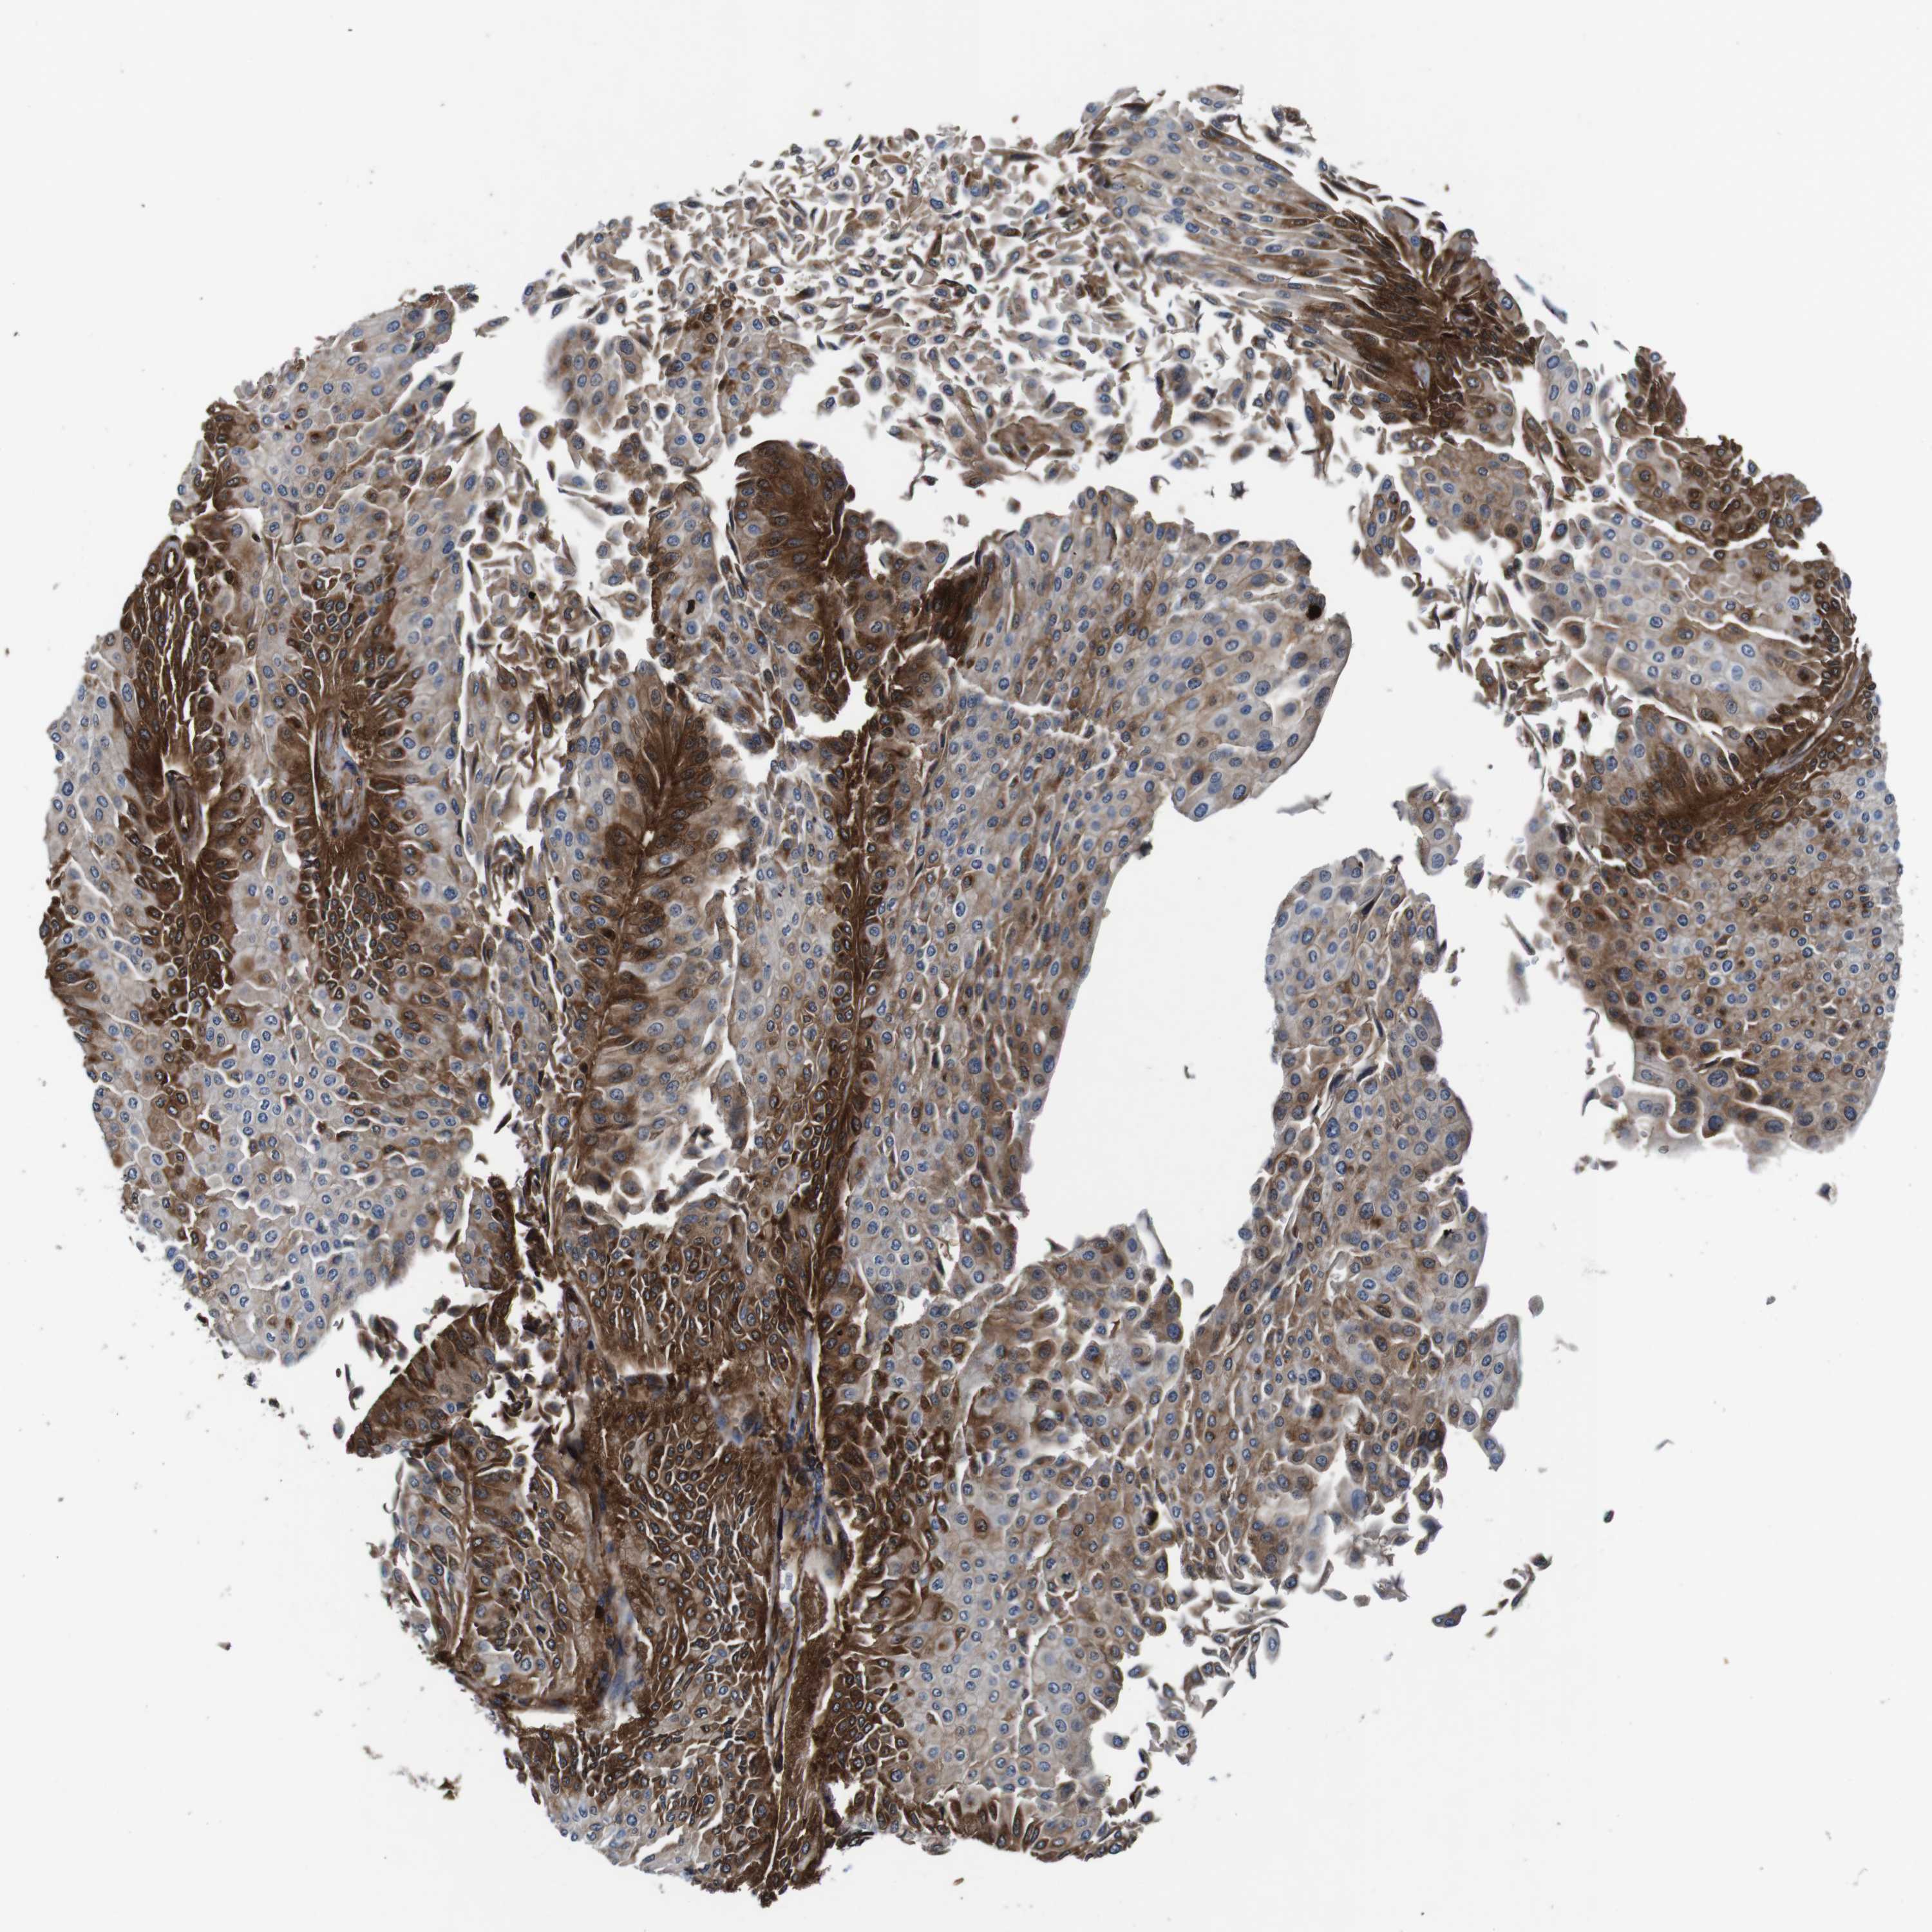

UROTHELIAL CANCER - Protein expressioni

A mouse-over function shows sample information and annotation data. Click on an image to view it in a full screen mode. Samples can be filtered based on level of antibody staining by selecting one or several of the following categories: high, medium, low and not detected. The assay and annotation is described here.

Note that samples used for immunohistochemistry by the Human Protein Atlas do not correspond to samples in the TCGA dataset.

Antibody stainingi

Antibody staining in the annotated cell types in the current human tissue is reported as not detected, low, medium, or high, based on conventional immunohistochemistry profiling in selected tissues. This score is based on the combination of the staining intensity and fraction of stained cells.

Each image is clickable and will lead to virtual microscopy that enables deeper exploration of all samples and also displays staining intensity scores, fraction scores and subcellular localization as well as patient and tissue information for each sample.

HPA011271

HPA011272

CAB013023

CAB035987

CAB058693

CAB080415

Staining

High

Medium

Low

Not detected

Intensity

Strong

Moderate

Weak

Negative

Quantity

>75%

75%-25%

<25%

None

Location

Nuclear

Cytoplasmic/membranous

Cytoplasmic/membranous,nuclear

Urothelial carcinoma, Low grade